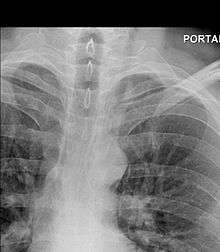

The diagnosis of Boerhaave's syndrome is suggested on the plain chest radiography and confirmed by chest CT scan. The initial plain chest radiograph is almost always abnormal in patients with Boerhaave's syndrome and usually reveals mediastinal or free peritoneal air as the initial radiologic manifestation. With cervical esophageal perforations, plain films of the neck show air in the soft tissues of the prevertebral space.

Hours to days later, pleural effusion(s) with or without pneumothorax, widened mediastinum, and subcutaneous emphysema are typically seen. CT scan may show esophageal wall edema and thickening, extraesophageal air, periesophageal fluid with or without gas bubbles, mediastinal widening, and air and fluid in the pleural spaces, retroperitoneum or lesser sac.